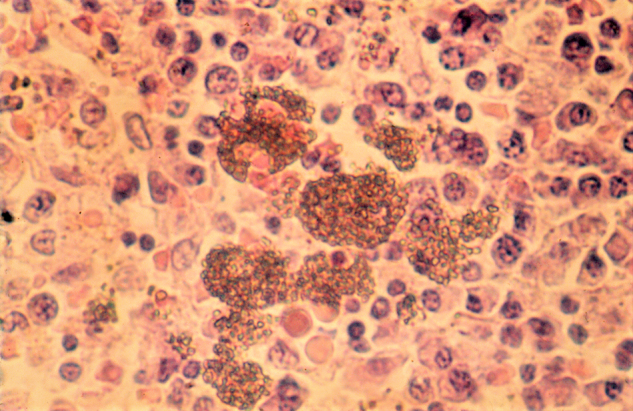

Abbildung 4.

Thorotrast-Partikel im histologischen Schnitt.

Zur Untersuchung der Spätfolgen wurden mehre Studien unternommen. Die zwischen 1968 und 2016 durchgeführte, größte retrospektive deutsche Langzeit-Kohortenstudie umfasste 2326 Thorotrast-Patienten und -Patientinnen und 1890 Patienten und Patientinnen einer angepassten Kontrollgruppe. Mithilfe epidemiologischer Erhebungen sowie klinischer, radiologischer und biophysikalischer Untersuchungen wurden die Spätfolgen insbesondere in Bezug auf die Krebsentstehung untersucht. (Abbildung 1, Abbildung 2, Abbildung 3, Abbildung 4, Abbildung 5, Abbildung 6)